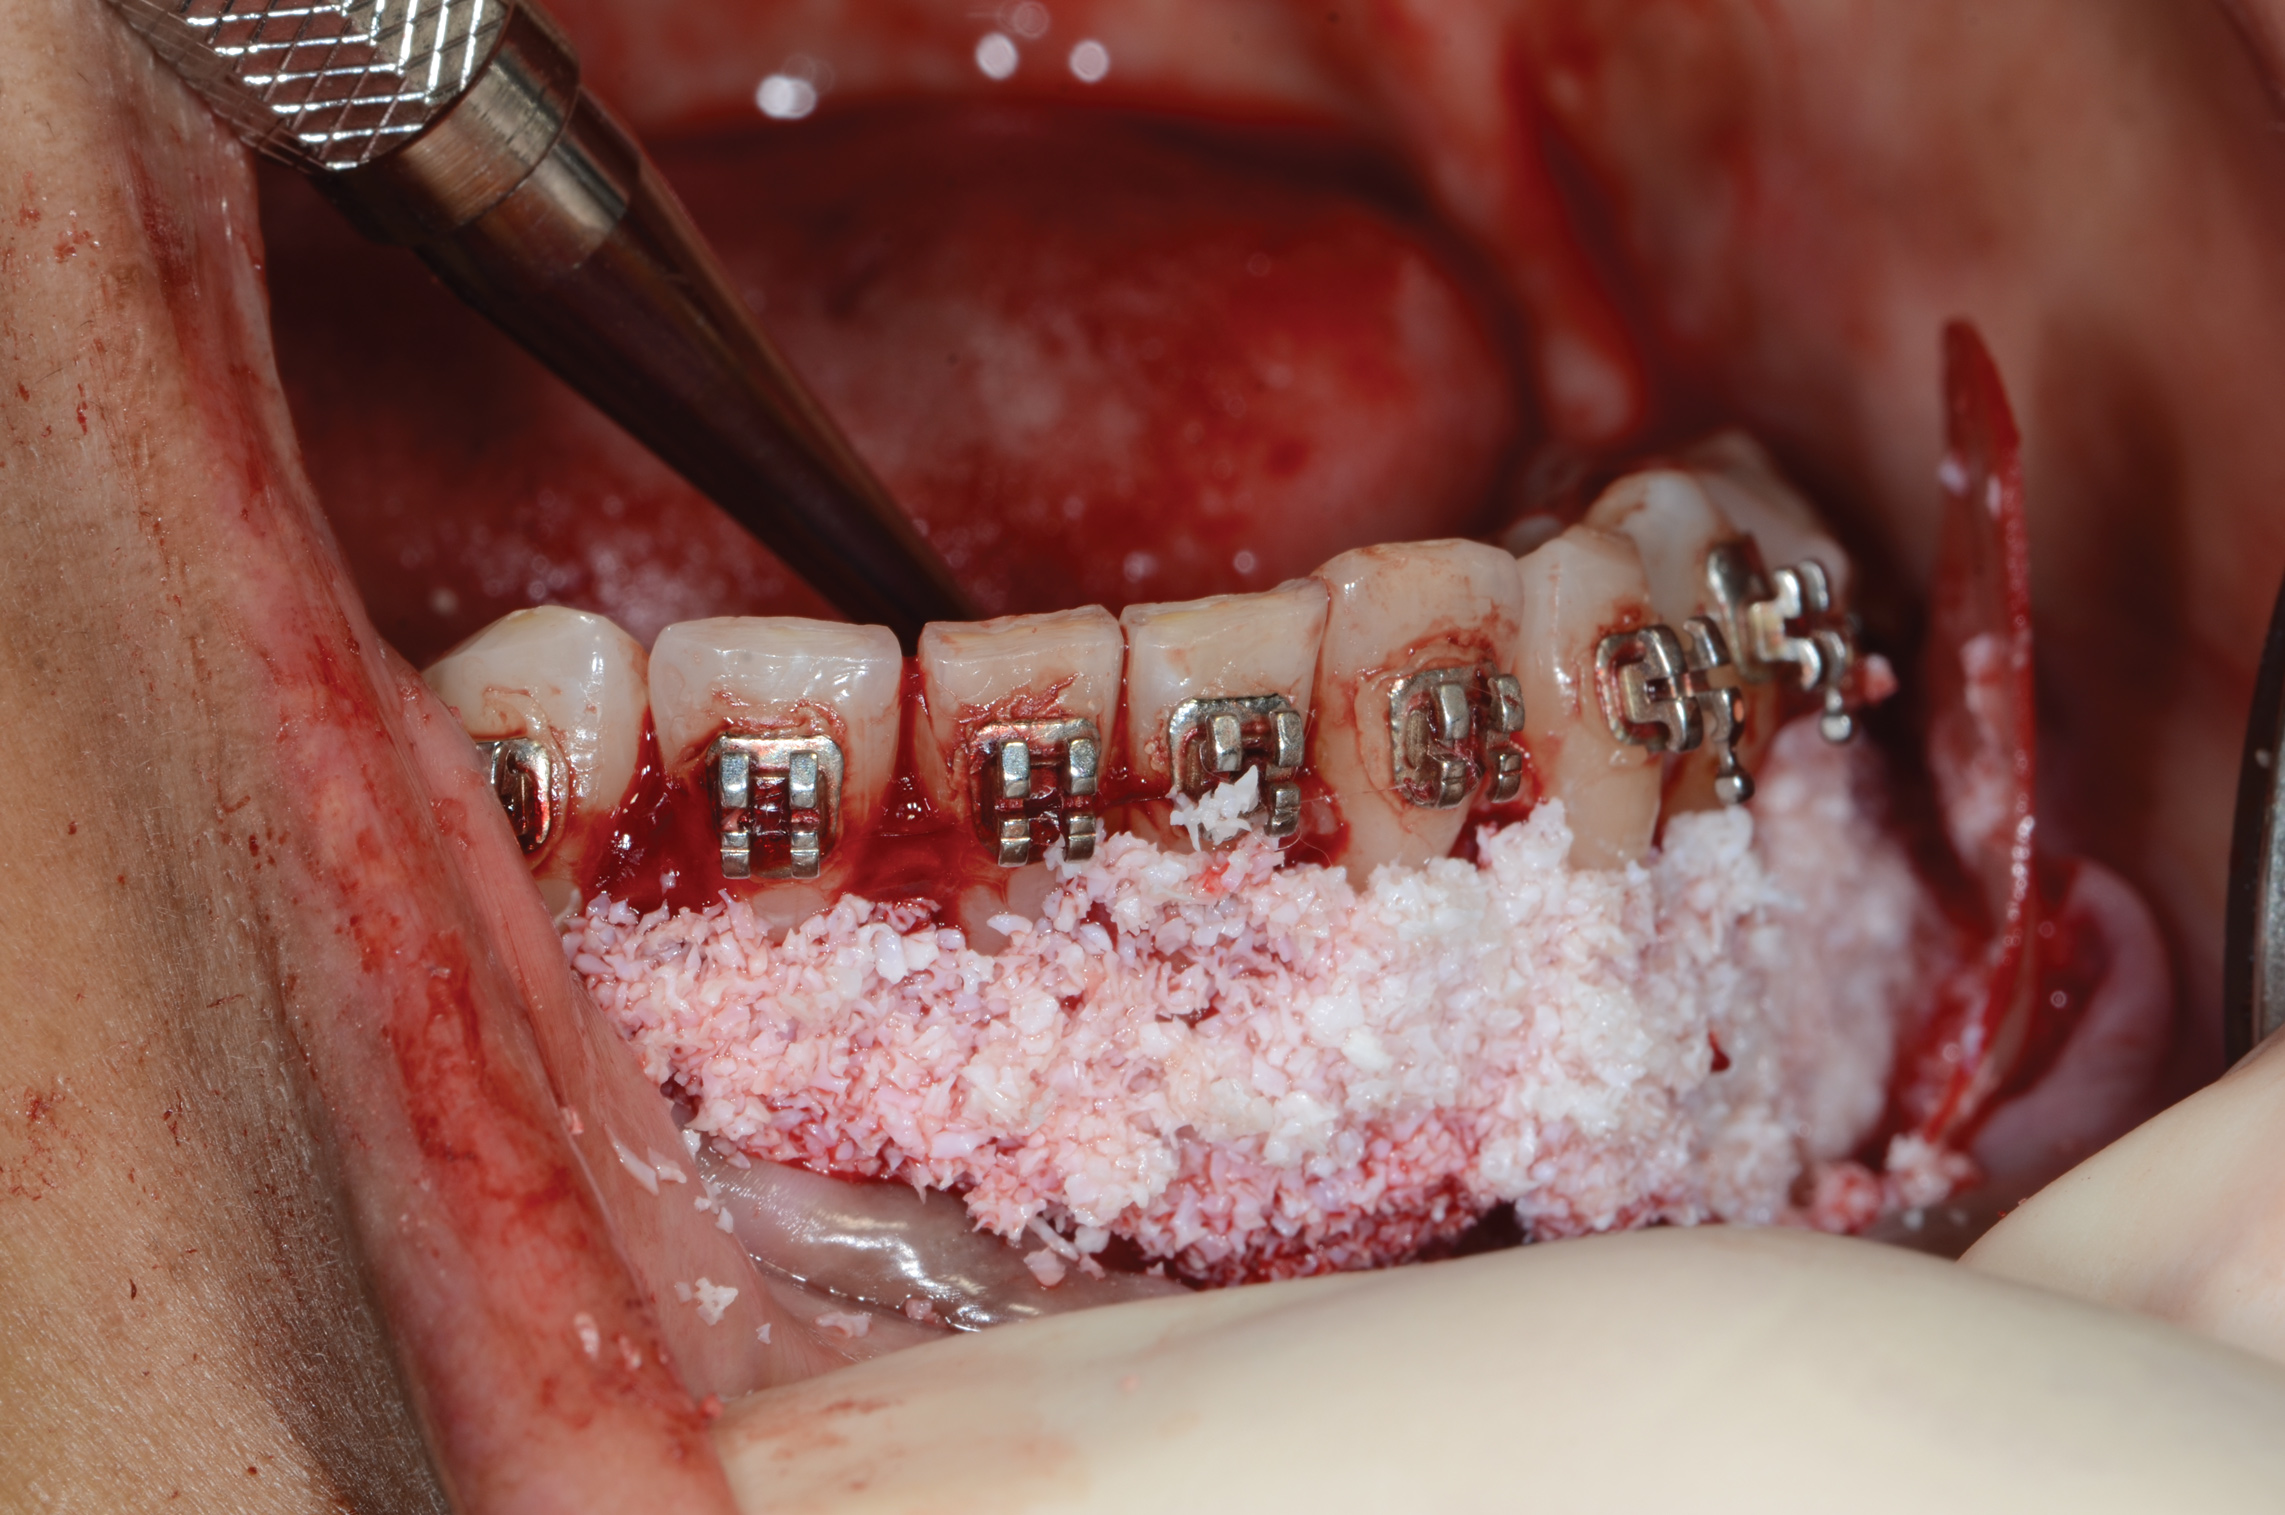

Fig 2. An abundant amount of bone biomaterial was placed during SFOT to compensate for anticipated graft shrinkage during healing.

Figure 2

Fig 3. Suturing after SFOT procedure; note the shallow vestibule post-closure.

Figure 3

Fig 4. A slight dehiscence of the flap was noted postoperatively. The prominent symphysis and associated strain of the mentalis muscle pull may have played a role in compromised soft-tissue healing.

Figure 4

Vertical facial pattern has been shown to be a determining factor in mandibular symphysis alveolar morphology as well as lower incisor positioning for both class I and class III patients.8 Also, it has been shown that short-faced class III patients have a widened alveolar bone.8 However, for long- and normal-faced class III patients, there is a natural compensation that elongates the symphysis and influences incisor position.8 Often this compensation is not only associated with thin alveolar bone but also may influence the strain and pull of the mentalis (Figure 1 through Figure 6).

Specific impact of muscle pressure on bone resorption has previously been shown where, after growth completion, muscle pressure exerted a resorptive effect on bone.9 Patients that were undergoing a forward-upward genioplasty, and therefore having the muscle pull released, showed an increased thickness of and more bone apposition above the symphysis.10

In general, the rate of developing soft-tissue complications related to bone augmentation procedures can range from 0% to 45%.22 In the anterior mandible any regenerative procedure that requires coronal positioning and primary closure can be challenging due to several anatomical factors (Figure 10 through Figure 13). These include the mentalis muscle pull; the depth of the vestibule, which should allow for primary closure without much tension on the lip; and the thickness of tissue, which should enable the primary closure to be maintained without dehiscence that may result in bone and membrane exposure.

In compromised situations where the depth of the vestibule is shallow or a prominent muscle pull exists, several complications can occur, including suboptimal closure with excessive tension around the lower lip area; soft-tissue dehiscence and opening of flaps resulting in loss of biomaterial that may compromise bone augmentation outcome and thickness during the healing phase and tooth movement; risk of infection due to exposure of bone and membrane/acellular dermal matrix, if used; and worsening of gingival recession due to soft-tissue dehiscence and loss of thickness at grafted sites.

Possible modifications in a patient with a shallow vestibule and prominent mentalis include preliminary vestibule deepening with the use of a free gingival graft or a Botox® injection to relieve muscle pull.